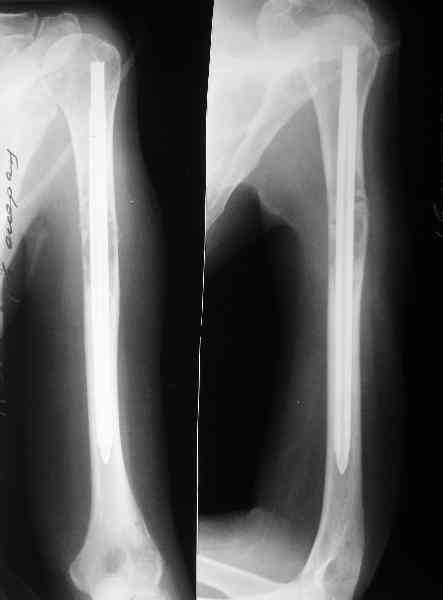

Женщина 53 лет получила патологический перелом правого плеча в феварле, и левого в марте - mts из невыясненного первичного очага.

Онкологи провели облучение, руки на косынки, время от времени наблюдают, вводили зомету.На нас вышли родственники. Состояние пациентки уже не очень, анемия (Hb -50-60 г/л), исхудалв, но асцита нет, в легких чисто. Поскольку женщина совершенно беспомощна, решили сделать остеосиннтез.

Сегодня сделали, Fixion диаметром 7,4 мм. Обе пперации продолжались по 7 мин. Картинки в приложении. Наркоз был диприваном, на спонтанном дыхании. По крайней мере, пока довольны хотя бы анестезиологи, похоже, не верили, что управимся меньше, чем за час ;-)

Гвоздик 7,4 расширяется до 11 мм. Не маловато ли, судя по снимкам?

7,4 мм, рсширяющийся до 11 мм, в принципе, достаточно для плеча. Хотя мне тоже показалось, что можно было бы и потолще. Вообще есть и следующий диаметр, 8,5 мм, расширяющийся до 13,5 мм, но его в наличии на сегодня не было.